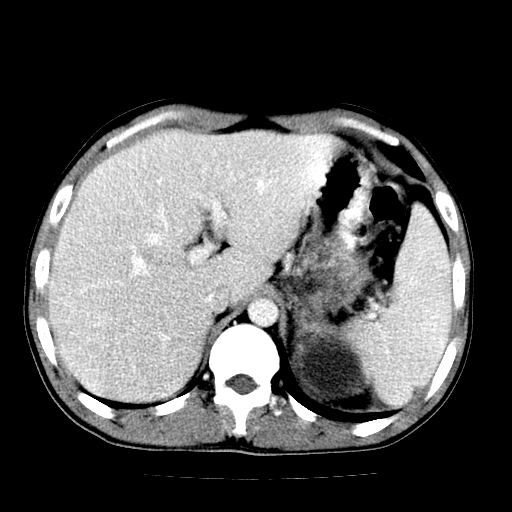

以下是引用天南地北在2007-4-30 13:36:00的发言:[br]支持慢性胰腺炎伴有假性囊肿

以下是引用andymaomao在2007-4-30 14:28:00的发言:[br]支持:1.慢性胰腺炎并假性囊肿形成可能;[br] 2.左肾形态稍增大,旋转不良。